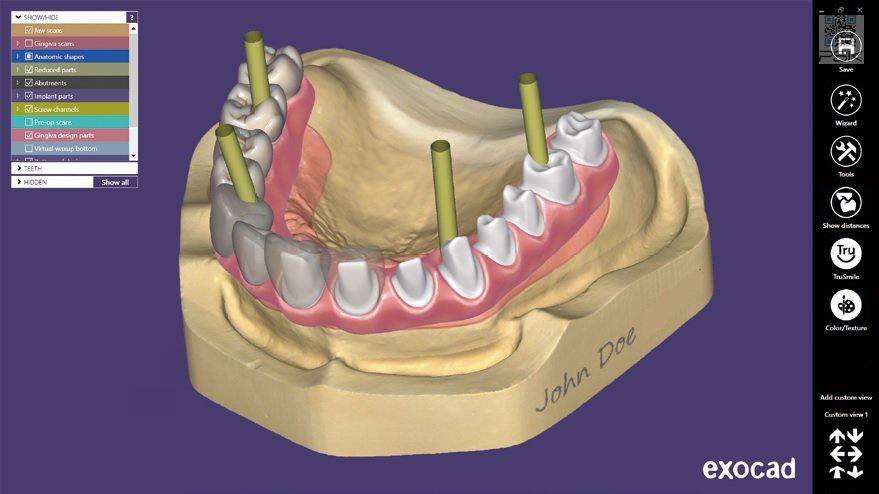

Концепция лечения All-On-4.

2. Цифровое планирование

моделируем положение имплантов

All-on-4 / "Все-на-четырех" – уникальное решение для пациентов с частичной и полной адентией, пародонтозом.

Методика позволяет установить пациенту несъёмный протез прямо

в день операции.